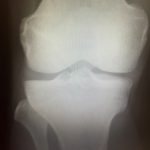

散々言われているようにレントゲンやMRI上の変化を痛みの原因とする損傷モデルは終わり、新しい考え方に変化しています。

レントゲンやMRIは、骨折や腫瘍、結核、結晶性関節炎などの鑑別以外は役に立たないどころか、患者にマイナスの観念を植え付けてしまい、ろくなことになりません。